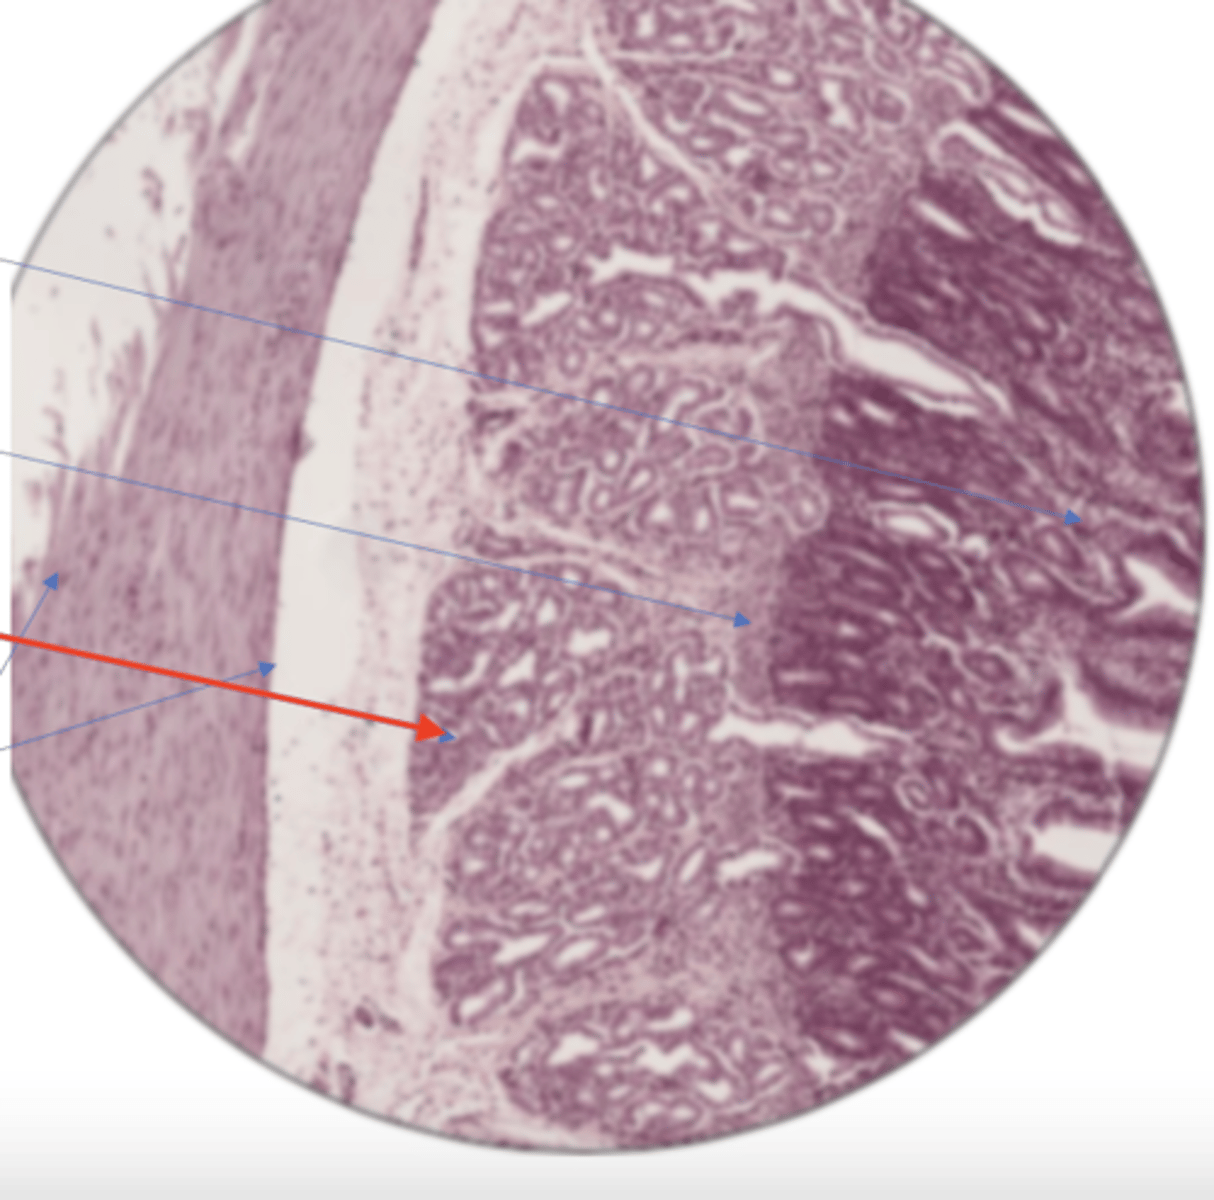

stomach mucosa

muscularis mucosa

stomach serosa

submucosa

gastric pit (stomach)

stomach mucosa layer (100)

stomach mucosa layer (400)